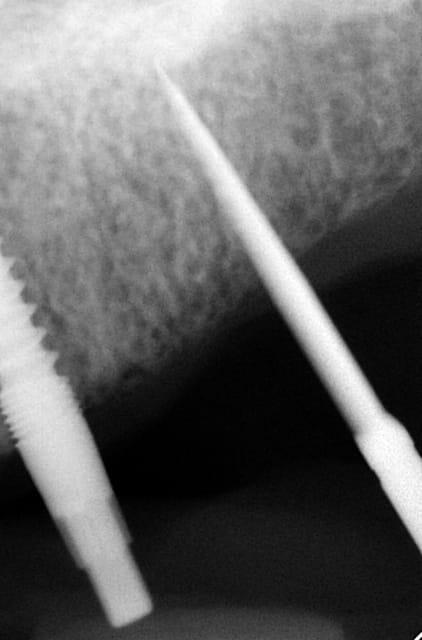

3ème photo: radio d´un patient âgé de 73 ans qui souhaitait avoir des dents fixées.Comme on l´observe il n a plus de place après les foramines mentales.Nous avons donc utilisé juste l´os interforaminal. Nous avons suivi le concept du prof. Nentwig qui consiste à pouvoir ajouter 2 dents dans chaque quadrant dans la mandibule.

Les forets utilisés ont 3 faces et sont coniques (250 trs/min) permettent une condensation de l´os et un traitement minimalement invasif.